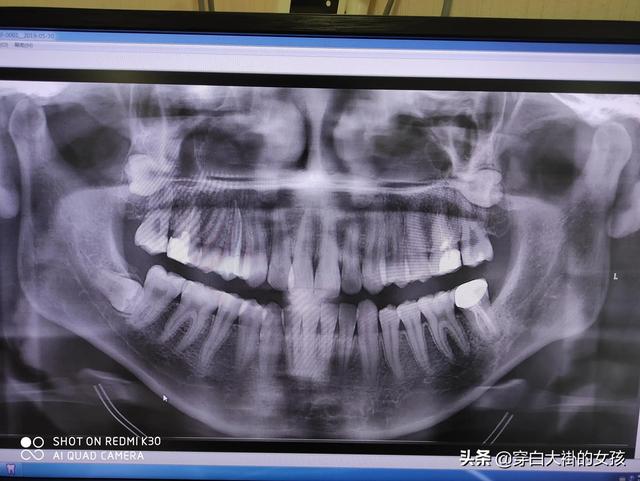

歯は人体の重要な器官であり、食べ物を噛むだけでなく、顔の美観を保ち、協調性を保ち、発音を助けるのが歯の主な機能である。

歯の機能 - 咀嚼

- 飲み込みやすいように食べ物を裂く;

- 噛むという行為は、歯の根の周りの神経を刺激し、脳を刺激して反射的に蠕動運動を調整する。同時に、胆嚢と膵臓からの消化液の分泌を促し、消化をさらに促進する。

歯の機能 - 調音を助ける

- 音は声帯によって生み出され、口や鼻腔を含むいくつかの器官によって調整され、私たちが理解できる言語を形成する。

- 歯がないと、言葉が不明瞭になる。歯がない場合、話し声が漏れます。

歯の機能 - 顔の美観と調和を保つ

人間の顔の視覚的知覚の60%~70%は顔の下1/3から来る。歯がまっすぐでない、口が突き出ている、宝天などであれば、顔の下1/3はよく見えない。顔の上半分が美しさを決め、顔の下半分が醜さを決める」ということわざがあるが、いくら五つの特徴の輪郭が良くても、口元の突出が深刻な問題である限り、その人の気質を際立たせることは非常に難しい。また、「顔立ちが整っていない」と思っていても、歯が欠けていたり、歯並びが不揃いだったりすると、さらに顔面価値を下げてしまう。